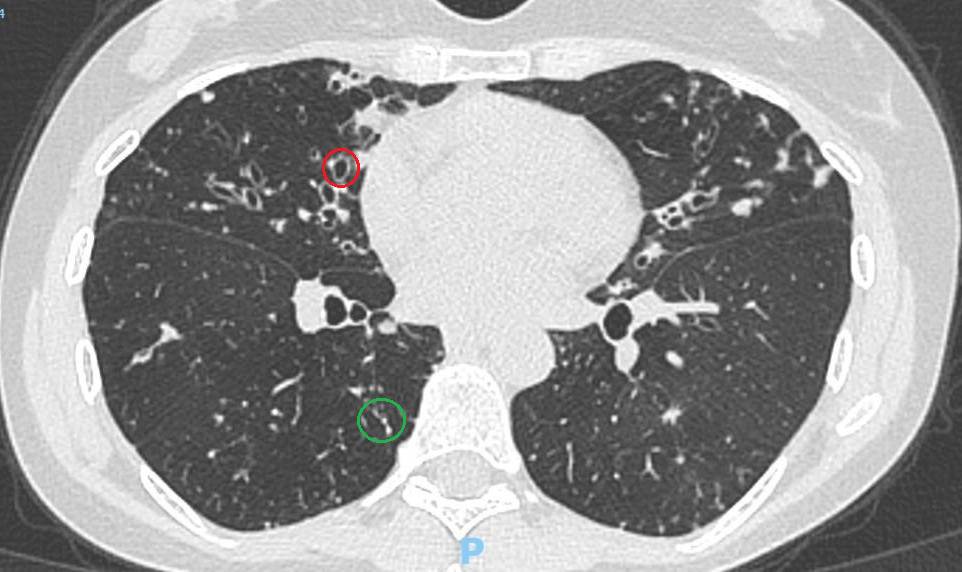

La característica principal desde el punto de vista de las imágenes pulmonares es la dilatación de los bronquios en comparación a las arterias bronquiales acompañantes. Esto suele detectarse al realizar una Tomografía Axial Computada de Tórax (como puede verse en la siguiente imagen, donde el círculo verde señala unos bronquios normales en el lóbulo inferior derecho y el círculo rojo indica bronquios muy dilatados compatibles con Bronquiectasias).